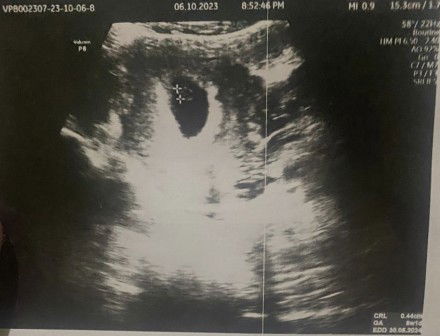

Bun mau tanya nih edd/hpl nya ko bnyak bgt ya yang bner yg mana?

Hpl di usg

dengerin yg dsebut Dr nya aja bund, banyak itu karna dilihat dari misal ukrn lingkar kepala perkiraan sekian, trs bwh lg misal dlihat dr panjang tulang / apa gt sekian. kalo ga salah gt aku dijelasin kmrn. ada jg misal dlihat dr uk perutnya debay gt. 🙏🏻

ga ush di baca,, patokan ny USG prtma kali aja,,, USG selanjutny cma untk liat bbj sma usia kehamilan,,